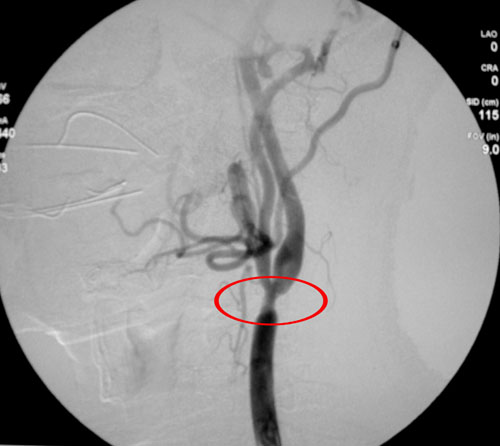

患者二:王某,男性,67岁。于入院前1年无诱因出现头晕,双眼黑朦,持续数分钟可自行缓解,数天发作一次,不伴有肢体麻木、无力等表现,当时未在意,未作任何检查及治疗。于2个月前(07年8月20日)再次发作,头晕缓解后出现右眼视力丧失入院。既往无高血压病史。体格检查:BP:125/90mmHg。右眼视力无光感。左眼视力0.4。余神经系统未见阳性体征。颈动脉血管超声检查:双侧颈总动脉粥样硬化斑块形成。右侧颈总动脉中~重度狭窄,左侧颈总动脉轻度狭窄。数字减影血管造影检查:右侧颈总动脉完全闭塞,左侧颈总动脉分叉处狭窄,狭窄率达(NASCET标准)90%。右侧大脑前、中动脉完全由左侧颈内动脉以大脑后动脉代偿.CT灌注成像显示:双侧脑血流量(CBF)、脑血容量(CBV)及平均通过时间(MTT)未见明显异常。CT平扫:未见异常。

诊断:1、短暂脑供血不足发作(TIA)2、动脉粥样硬化左侧颈动脉狭窄、右侧颈动脉闭塞 。

处理方法:术前予以扩血管、改善微循环以及抗血小板凝聚治疗。病情平稳。无TIA发作。先为其实施右侧的颈动脉内膜剥脱术(CEA),待恢复数月后再实行左侧手术,手术进展十分顺利,血运得以恢复,患者几尽失明的右眼在术后1小时又重见光明,能清楚辨别物体,视力恢复达1.0。

这种一侧颈动脉狭窄对侧闭塞的患者,自然预后较差,一旦术中不能在很短的时间内恢复血流,相应组织就会缺血出现症状,有关其手术治疗的报道一直是很不乐观的。根据NASCET试验的数据显示,对侧闭塞病变可以作为一个独立的危险因素,影响症状性颈动脉病变重建手术的效果,导致手术结果很差。近年来随着外科以及麻醉技术的逐渐改进和提高,外科医生们也越来越多地尝试对这种患者采取手术治疗。目前又有新的和确凿的证据显示对于症状性颈内动脉闭塞的患者,对侧的CEA手术对于其双侧半球的恢复都是有益的。但是由于手术的风险性加之对技术的要求很高,因而在医学界一直是一个有待突破的禁区。这例手术的成功,创造了一个医学奇迹!